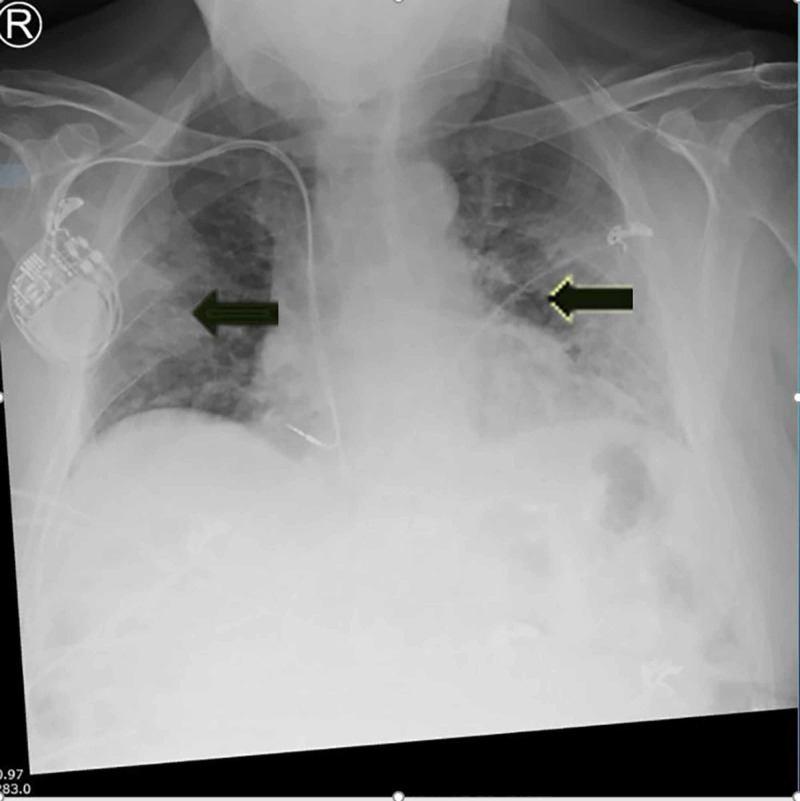

The previously well man reported a past medical history of asymptomatic and stable prostate cancer, as well as treated melanoma five years ago. He presented with a five-day history of fever, cough, shortness of breath, anorexia and sore throat to the ED in late March 2020. The patient had not travelled overseas and had no history of contact with any known case of COVID-19. He was febrile on admission with a temperature at 38.2° C, displaying slight tachypnoea (respiratory rate of 22) and a blood oxygen saturation of 95%. His blood pressure and heart rate remained stable upon arrival at the ED. His initial chest X-ray revealed patchy opacities in the mid to lower lung fields (Figure 2), indicating a likely diagnosis of COVID-19.

Figure 2. Bilateral chest X-ray on admission showing basal opacities secondary to COVID-19-associated pneumonia .

Arrowheads demonstrate the bilateral, patchy opacities in the lungs